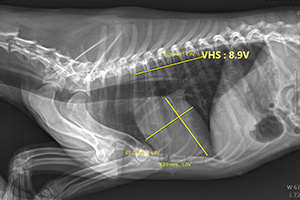

椎体测量系统(Vertebral Scale System,VSS)研究的重点在于心脏大小和椎体长度的比较。该系统将心脏的长、短轴用从第4胸椎开始的椎体长度表示,其结果表示为椎体心脏比分(Vertebral Heart Size,VHS)。

2、VHS的测量

T-气管

L-心脏长轴,从气管分叉处腹侧至心尖的距离

S-心脏短轴,从心后缘与后腔静脉相交处的中点引长轴的垂线至心前缘的距离

L和S以从T4开始的椎体长度表示(估计至0.1 v),相加即为VHS。

VHS=L+S

如图所示,L=5.8v,S=4.6v,VHS=L+S=10.4v。

3、X线片的实际测量

如上图,VHS=5.7v+4.5v=10.2v